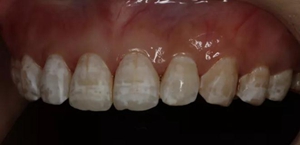

2,使用紅標45μm微米和黃標25μm粒度車針仔細緩慢打磨去除釉質(zhì)表面高氟鈣化的斑塊和釉質(zhì)凹坑0.05-0.1mm后,車針打磨后要再使用低速慢機用矽粒子拋光去除釉質(zhì)表面浮釉(松風矽粒子、樹脂拋光輪),下圖是微打磨后。

(下圖是上頜打磨后與下頜術前未研磨對比,區(qū)分打磨效果和目的)